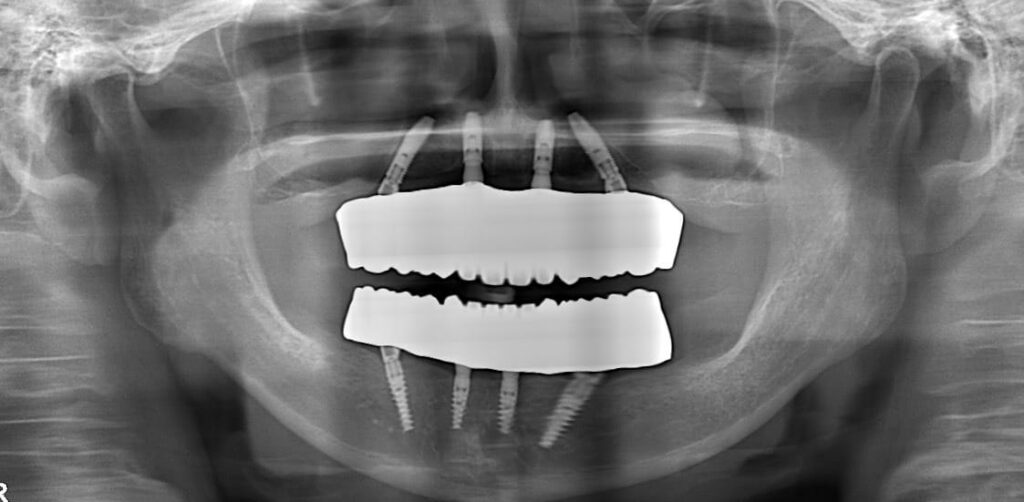

パノラマX線写真

Before

After

術後のCT

術前の治療計画通りの位置に、インプラントを埋入する事が出来ました。

このように、ボーンリダクションを伴う、抜歯即時荷重症例において、Xガイドを用いることで、非常にシンプルな手術が行え、従来法(サージカルガイド)より正確な手術を行う事が可能となります。